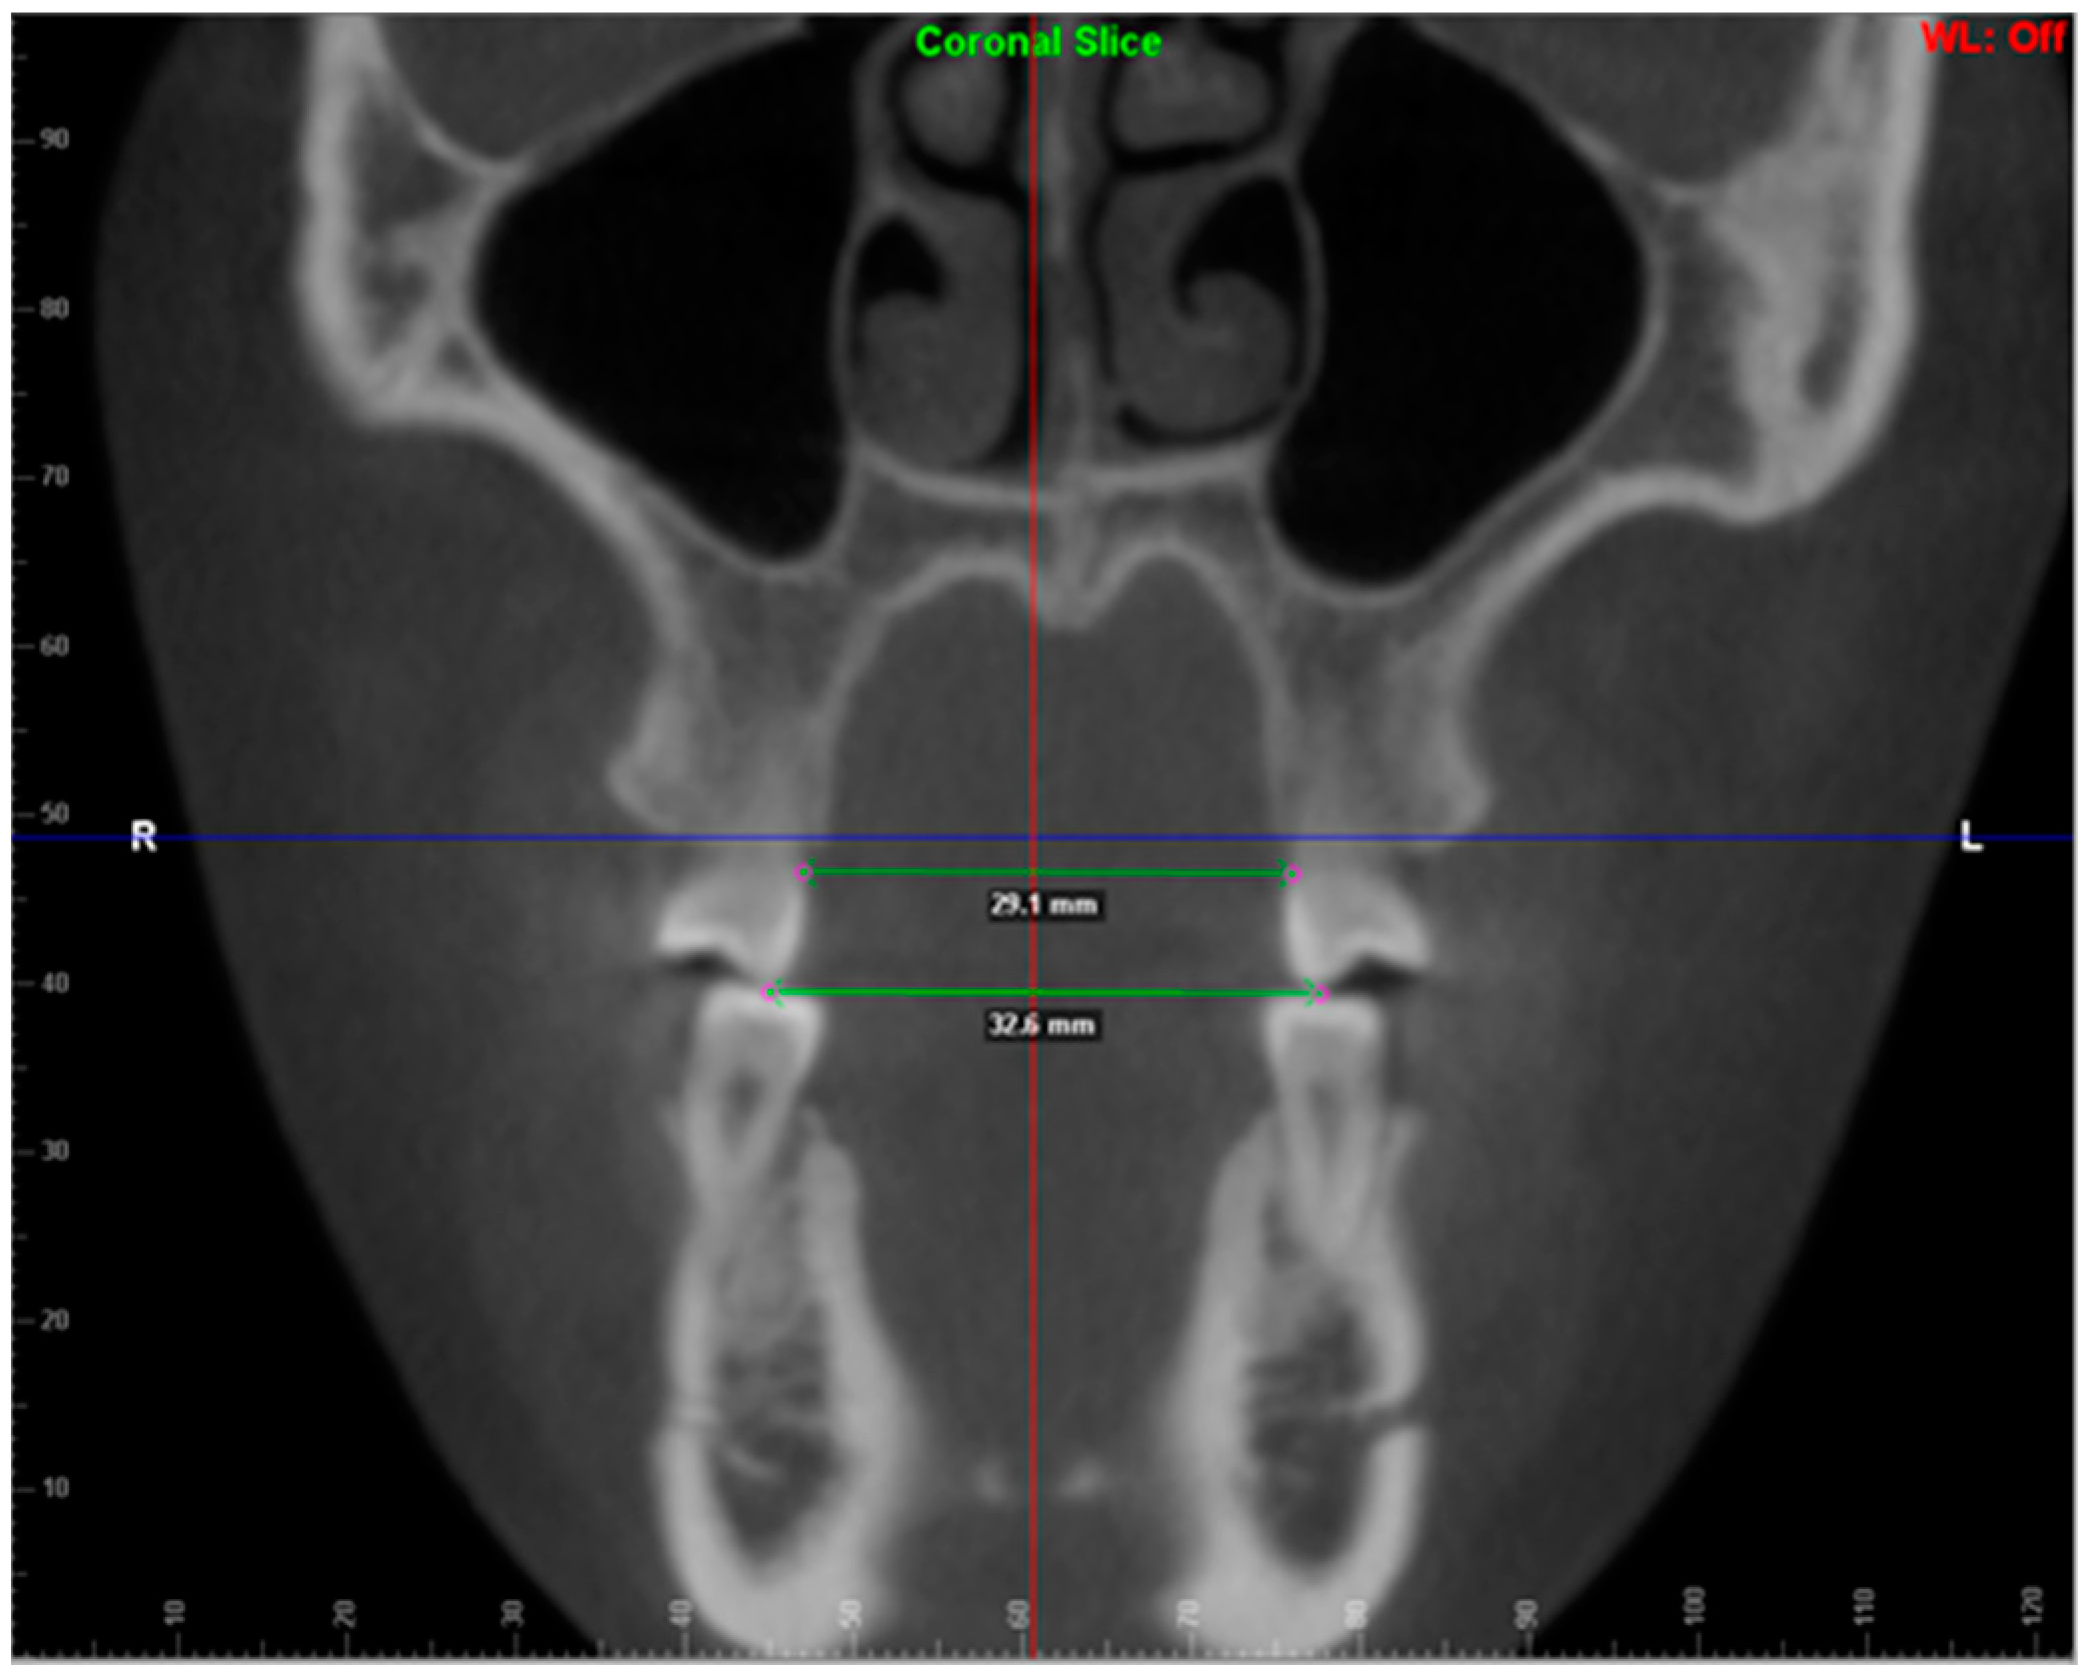

2. Materials and Methods